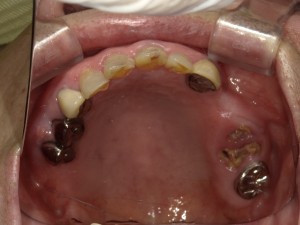

30代 女性 奥歯 インプラントGBR

| 年代・性別 | 30代・女性 |

| 治療回数 | 1回 ※術前治療・検査除く |

| 治療期間 | 5ヶ月 |

| 料金 | ¥60,000(税込) |

GBR(Guided Bone Regeneration:骨再生誘導法)とは、インプラント治療において、骨の厚みや高さが足りない場合に行う歯槽骨を再生する方法です。骨量不足の患者様でも、骨造成を行うことでインプラントの埋入に必要な骨の高さや厚みが得られます。 GBR(再生誘導法)は、骨が痩せて十分な骨量が確保できない患者様に、骨の再生によってインプラントの埋入を可能にする治療方法の一つです そのような骨が欠損した部分では、骨を作る「骨芽細胞」よりも、骨にならない「線維芽細胞」の方が増殖しやすいという特徴があります。そのためGBRでは、骨形成の妨げになる繊維芽細胞の侵入を防ぐため、骨を増やしたい部分を「メンブレン」という人工膜で覆い、その中に自家骨や人工の骨補填材を詰めて骨芽細胞の増殖を促します。 |

| 副作用 | 術後に腫れ・痛みが出る可能性がある。 |